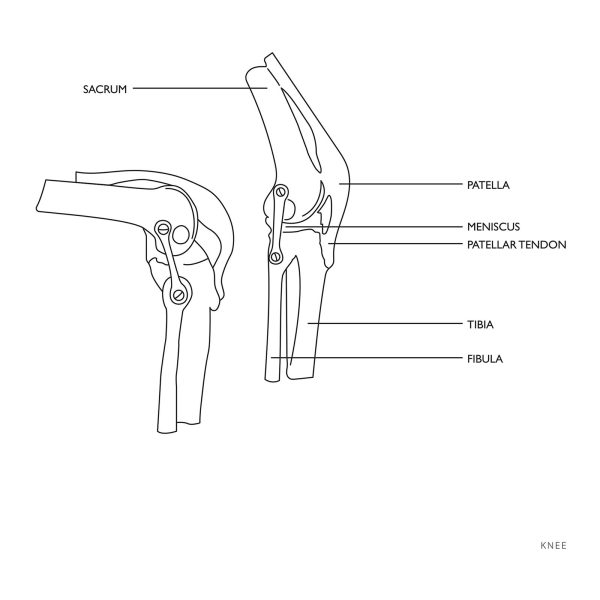

1: 1 ceļa locītavas anatomiskais modelis

Physa ceļgala dīķa anatomiskais modelis ir uzticīgi reproducēta kustīga triviāla kopija, kas tiks izmantota skolās, ārstu birojos un medicīnas universitātēs. Produkts uzrāda šādus kaulu Lielbritānijas elementus, piemēram, patella, locītavu virsmu, sāniski, kaulu, stilba kaulu un pierādīja, un tā:

– aizmugurējais krusts,

– Sānu stilba kauls,

– priekšējais krusts,

– puse,

Mēroga modelis 1: 1 ir izgatavots no izturīga plastmasas izturīga pret dīķi un bojājumiem. Viņš tika krāsots ar augstas kvalitātes krāsām, kas gadiem ilgi saglabā viņa krāsu. Tika izmantoti visi nerūsējošā tērauda berzes. Par stabilu produktu rūpējas ar taisnstūra pamatni.

Produkta īpašības: â – Precīza veiktspēja – vislabāk reproducētais plecu locītavas anatomiskais modelis tirgū,

– telpums – iespēja redzēt locītavu katrā pusē